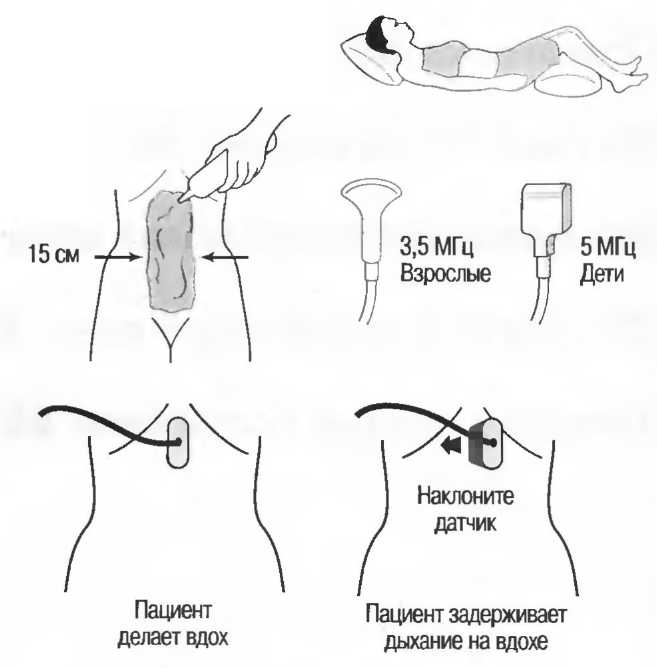

Затухание

Ткани тела поглощают и рассеивают ультразвук по-разному. Высокие частоты поглощаются и рассеиваются (гасятся) в большей степени, чем низкие. Поэтому, чтобы достичь более глубоких тканей, необходимо использовать более низкие частоты, так как менее вероятно, что эти волны затеряются при прохонодении через ткани. На практике оптимально использовать частоту около 3,5 МГц для глубокого сканирования у взрослых и частоту 5 МГц и выше для исследования более худых пациентов или детей. Частота 5 МГц и выше используется для исследования поверхностных органов у взрослых.

Выбор соответствующего датчика

Наилучшим датчиком для общей практики является конвексный датчик с частотой 3,5 МГц с фокусировкой на расстоянии 7-9 см. Если такого датчика нет, необходимо наличие линейного секторного датчика с частотой 3,5 МГц. При необходимости исследования детей и худых взрослых желательно дополнить набор датчиком с частотой 5 МГц с фокусировкой 5-7 см.

1. Ультразвуковые исследования в акушерстве. Для общих исследований в акушерстве используется линейный или конвексный датчик с частотой 3,5 или 5 МГц с глубиной фокусировки на 7-9 см. Если закупается только один датчик, выбирайте датчик с частотой 3,5 МГц. Датчик с частотой 5 МГц предпочтителен на ранних сроках беременности. В поздние сроки беременности лучше использовать датчик с частотой 3,5 МГц.

2. Ультразвуковые исследования в общей практике. Если проводятся исследования в верхней части живота и таза у взрослых, в том числе и акушерские исследования, предпочтительнее выбор секторного или конвексного датчиков с частотой 3,5 МГц с глубиной фокусировки на 7-9 см.

3. Ультразвуковые исследования в педиатрии. Для детей необходим датчик с частотой 5 МГц с глубиной фокусировки на 5-7 см. При исследовании мозга новорожденного используется секторный датчик с частотой 7,5 МГц с глубиной фокусировки на 4-5 см (этот датчик также используется для исследования яичек и структур шеи у взрослых).